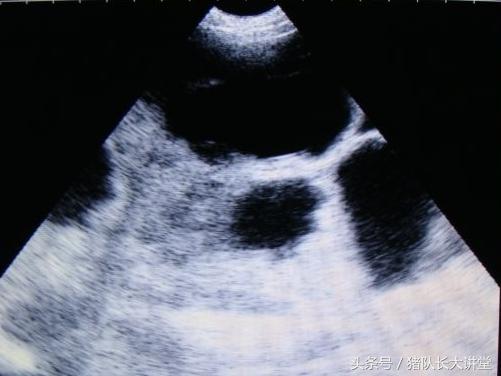

中间的黑球是初期胚胎

A、可以较为准确的测出是不是有小猪,具体使用办法,根据说明使用,大家也可以提出问题;注意,一般你检测有的就是有了,单是检测没有的时候应该多观察;